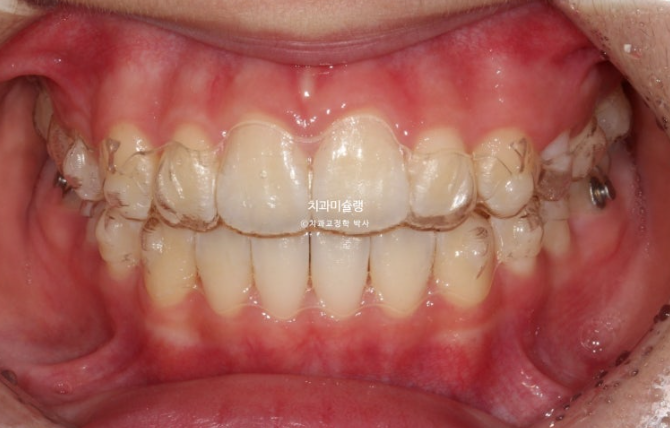

25.04

드디어 남은 유치가 다 빠졌습니다.

돌출 개선을 조금 더 도모하고자 두번째 세트 장치 제작에 들어갑니다.

사이즈가 큰 앞니를 미량의 치간삭제를 통해 줄이고 앞니 각도도 좀 더 개선하기로 합니다.

두번째 세트 장치는 15개가 나왔고 25년 11월까지 6개월간 장치를 열심히 껴주고 드디어 치료를 마무리 했습니다.